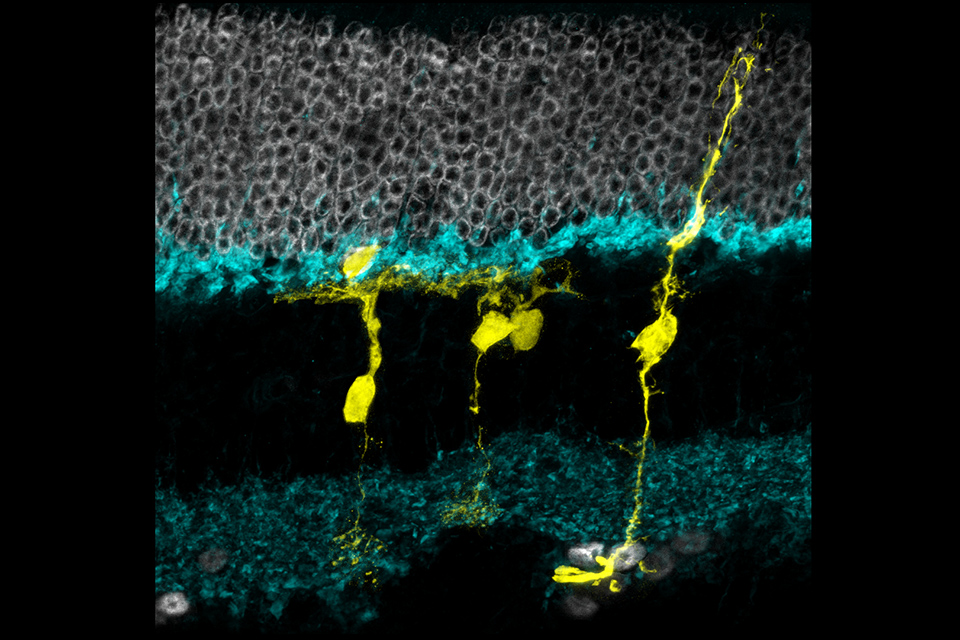

Regenerative Potential of Cells

Regenerative Potential of Cells